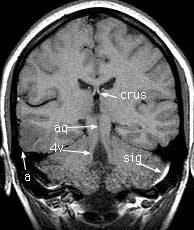

Findings: Focus of low signal in the cortex of the right middle and inferior temporal gyri (a). Cerebral aqueduct (aq) leading from the 3rd (3v) to the 4th (4v) ventricle. Crus of the fornix (crus). Flow enhancement in the sigmoid sinus (sig). Superior (stg), middle (mtg) and inferior (itg) temporal gyri. Hippocampus (hip). Body of the corpus callosum (body). Insula (in). Cerebellar tonsils (ton). Cingulate gyrus (cgy) and sulcus (csu). Body of the caudate nucleus (caud). Horizontal fissure (hor).